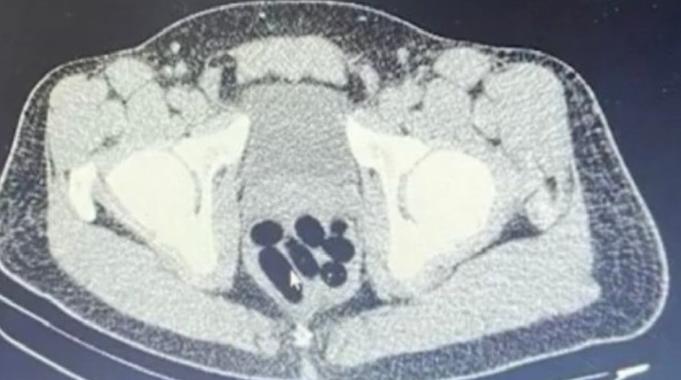

Gözaltına alınan şüphelinin hastanedeki iç beden muayenesinde 77 adet kapsül şeklinde 1 kilo 134 gram narkotik madde ele geçirildi.

Şüphelinin midesindeki maddeler cerrahi müdahale ile çıkarılırken hakkında uyuşturucu madde ticareti yapmak suçundan adli işlem başlatıldı.